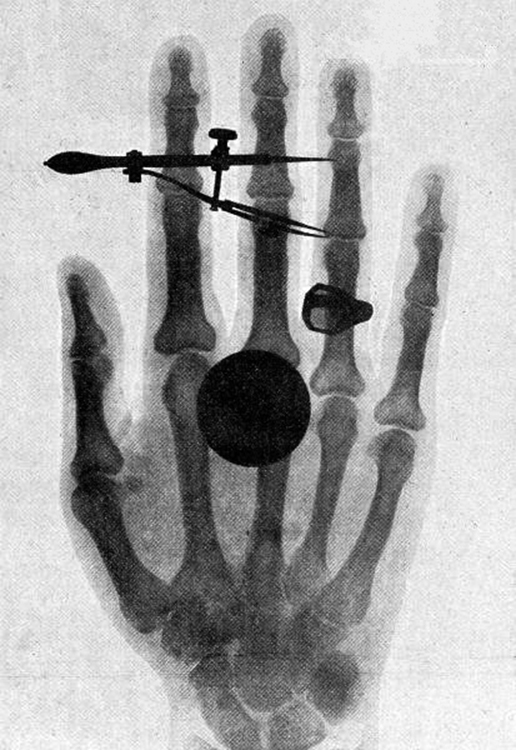

Figure 29.12 One of the first x-ray images, taken by Röentgen himself. The hand belongs to Bertha Röentgen, his wife. (credit: Wilhelm Conrad Röntgen, via Wikimedia

Commons)

High photon energy also enables γ rays to penetrate materials, since a collision with a single atom or molecule is unlikely to absorb all the γ ray’s

energy. This can make γ rays useful as a probe, and they are sometimes used in medical imaging. x rays, as you can see in Figure 29.11, overlap with the low-frequency end of the γ ray range. Since x rays have energies of keV and up, individual x-ray photons also can produce large amounts

of ionization. At lower photon energies, x rays are not as penetrating as γ rays and are slightly less hazardous. X rays are ideal for medical imaging,

their most common use, and a fact that was recognized immediately upon their discovery in 1895 by the German physicist W. C. Roentgen

(1845–1923). (See Figure 29.12.) Within one year of their discovery, x rays (for a time called Roentgen rays) were used for medical diagnostics.

Roentgen received the 1901 Nobel Prize for the discovery of x rays.